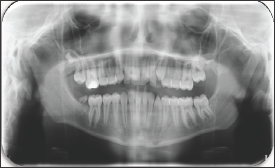

The case of erupted complex odontoma in mandibula was reported in this paper. The clinical and radiological examinations of a 12-year-old girl referred to the pediatric dentistry clinic with complaints of pain in the right mandibular region were performed. In the anamnesis taken from the patient, it was learned that she had no systemic disease. During her intraoral examination, a tooth-like tissue was observed inside of the gingiva in the right mandibular posterior region (Figure 1). No inflammation or ulceration was found in the mouth. During radiographic examination, it was observed that the patient's tooth number 47 was congenitally missing (Figure 2). The pre-diagnosis of complex odontoma was made after the clinical and radiological examinations. The patient was taken under an operation under local anesthesia and was operated with surgical procedures. As a result of the histopathological examination of the biopsy material obtained, the complex odontoma in opaque color with a dimension of 0.8x0.7x0.7 cm was confirmed (Figures 3-4).

Figure 2: Pre-Operative Panoramic Film.